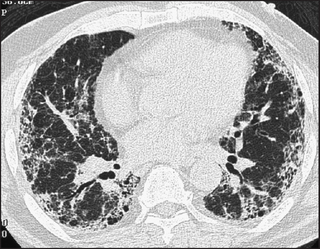

High-resolution CT scans give more detailed information about the lungs but expose the patient to hundreds of times more radiation. They are particularly useful for diagnosing interstitial lung disease, pulmonary haemorrhage (see Figure 12.13) and bronchiectasis (see Figure 12.14). Primary and secondary lung tumours are best imaged with CT and tuberculous involvement of the lungs can be quantified (see Figure 12.15).

Figure 12.14 (a) to (c) Bronchiestasis (From Mettler FA. Essentials of radiology, 2nd edn. Saunders 2005.)